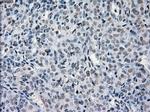

PRKY Monoclonal Antibody (OTI3E10), TrueMAB™

A group of proteins that are intimately involved in this process are the serine/ threonine (Ser/Thr) protein kinases. PRKY (protein kinase, Y-linked) and PRKX (protein kinase, X-linked) are members of the Ser/Thr protein kinase family, both of which belong to the subfamily of cAMP-dependent kinases. Encoded by a gene that is located near the pseudoautosomal region on chromosome Y, PRKY contains one protein kinase domain through which it catalyzes the ATP-dependent phosphorylation of target proteins. Functioning in a similar manner to PRXY, PRKX contains one protein kinase domain and is essential for macrophage differentiation and renal epithelial cell migration. Defects in the genes encoding PRKY and PRXX are associated with sex reversal disorder, namely XX in males and XY in females.